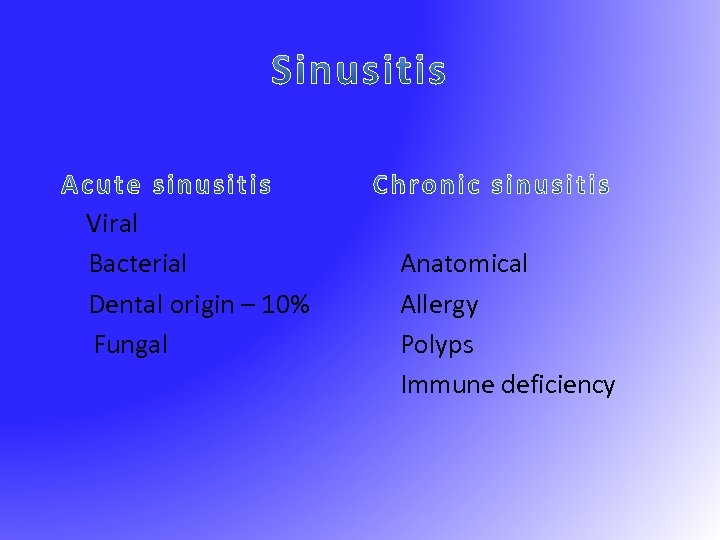

Viral Bacterial Dental origin – 10% Fungal Anatomical Allergy Polyps Immune deficiency

Viral Bacterial Dental origin – 10% Fungal Anatomical Allergy Polyps Immune deficiency